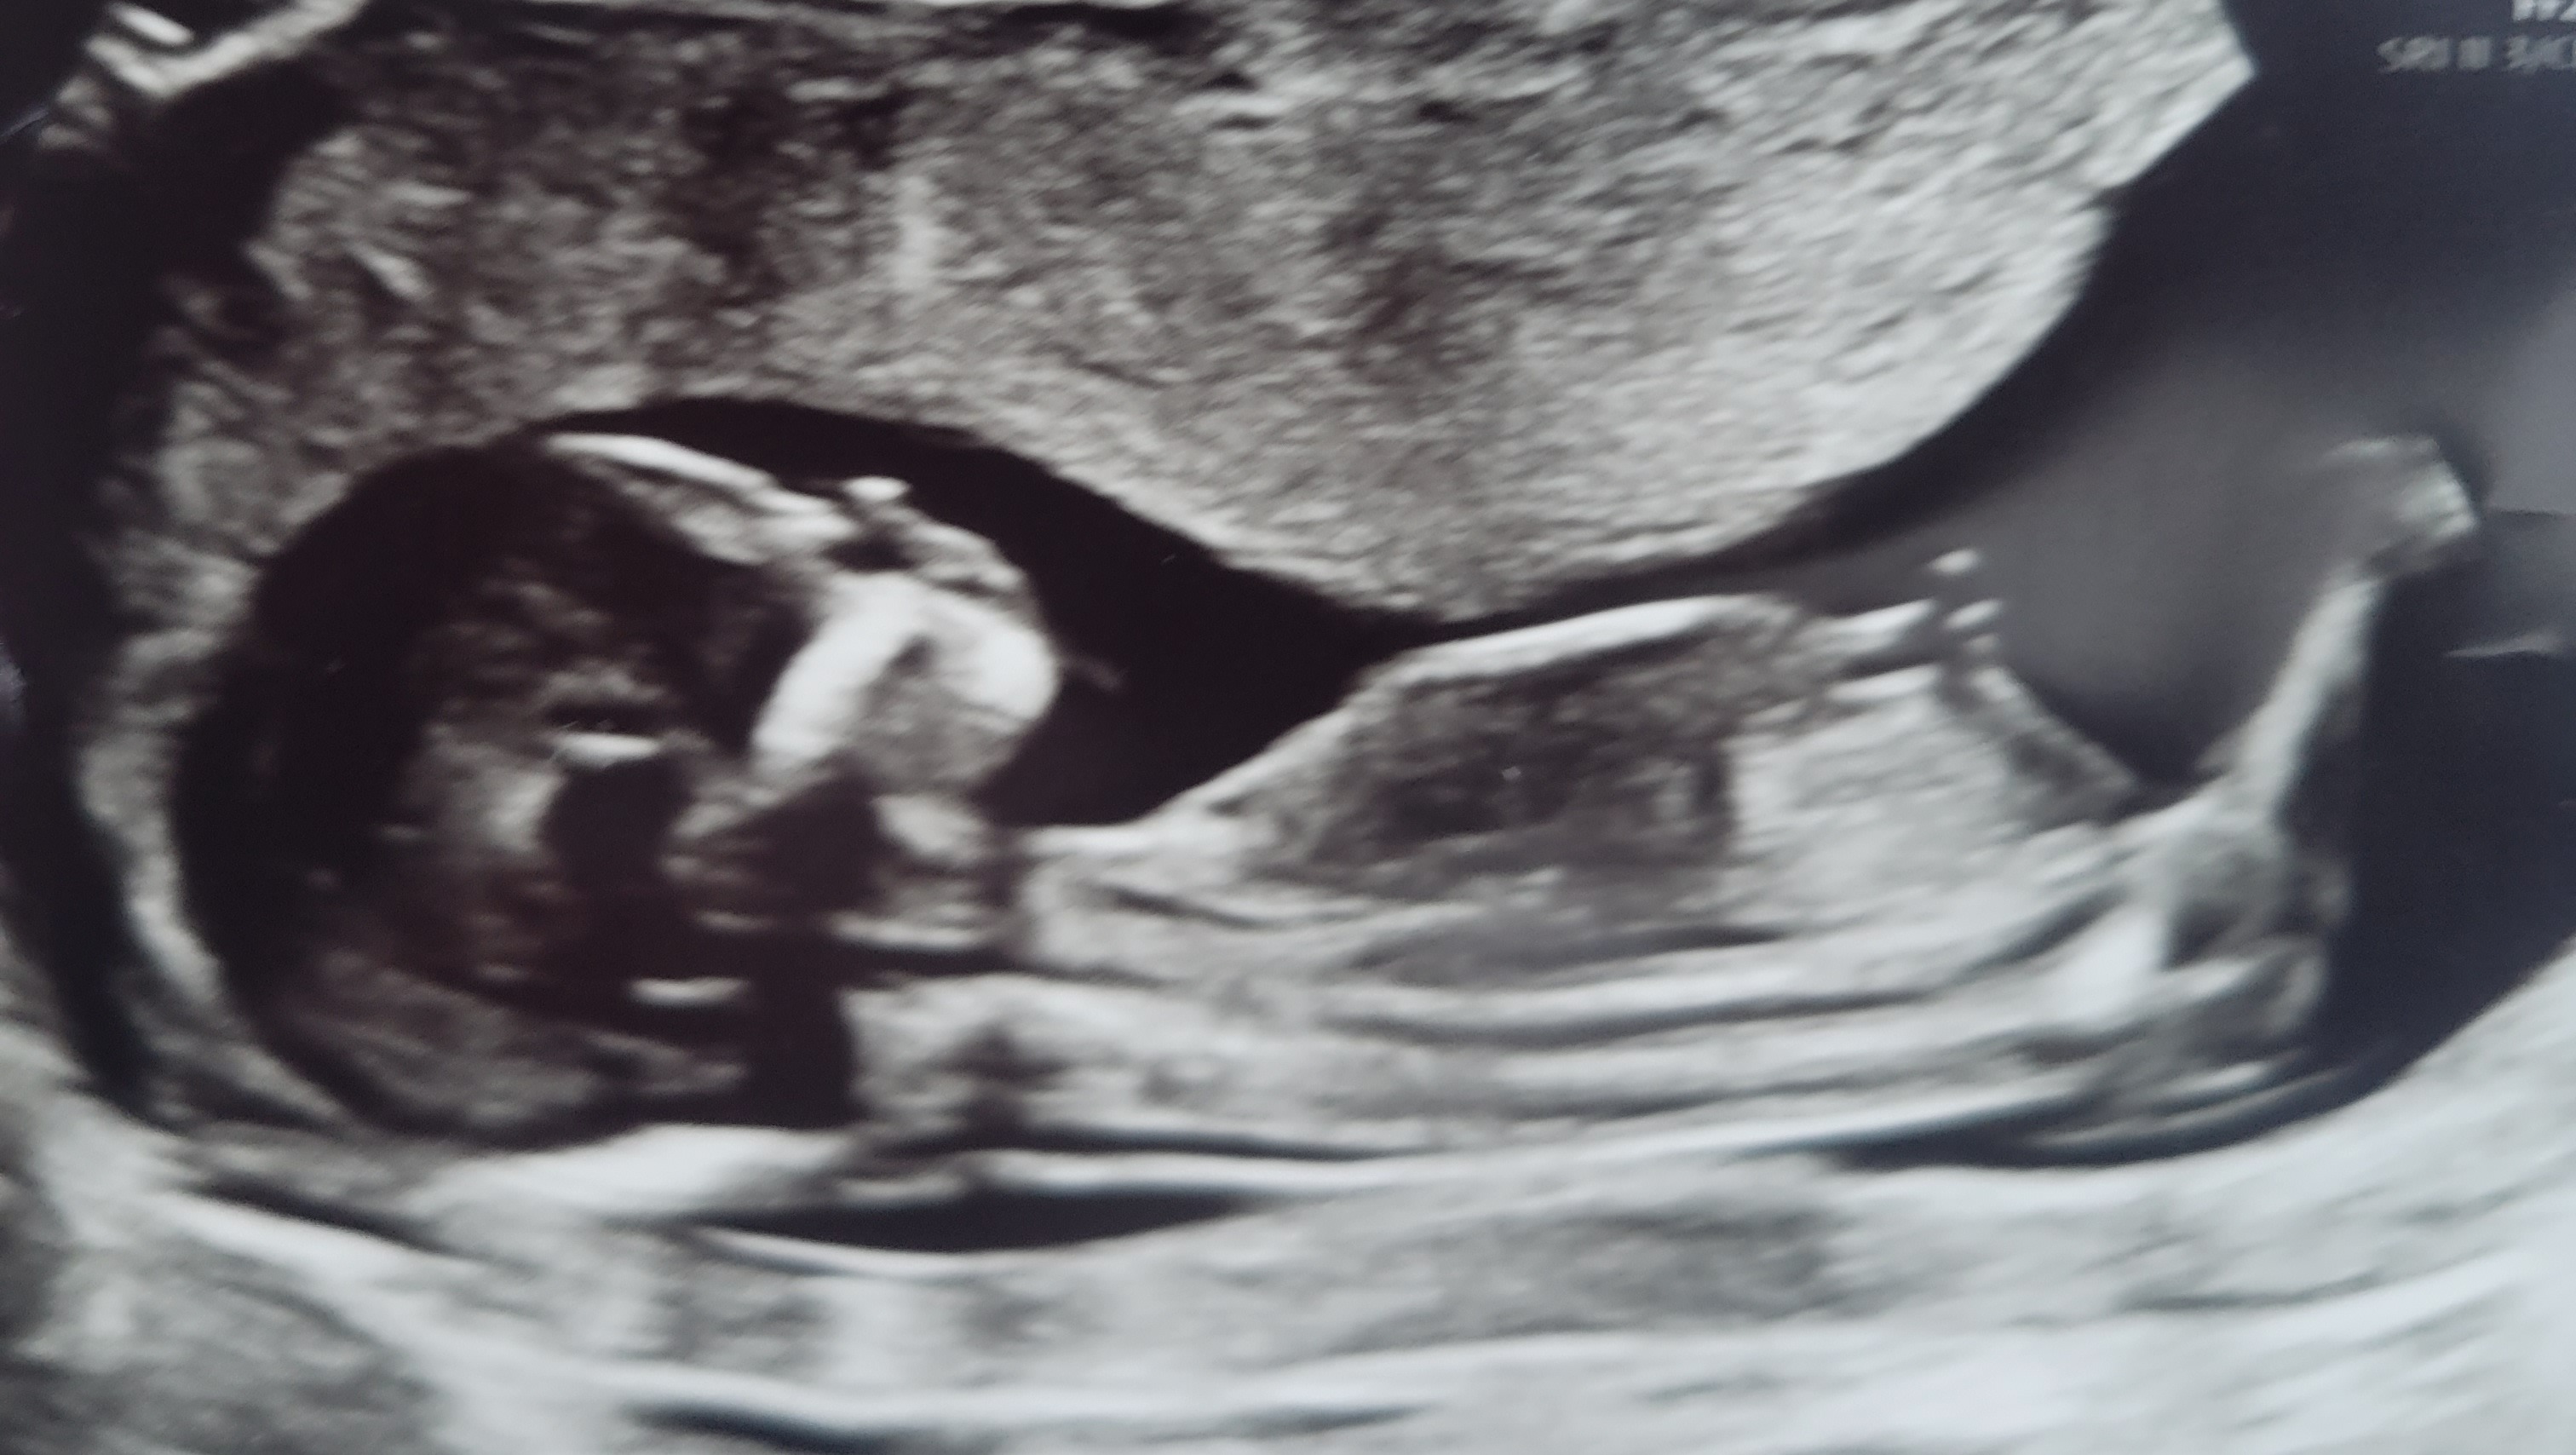

After 12 years of trying, infertility treatments, a failed IVF cycle and a miscarriage last year, we were thrilled to find out we were expecting again on December 15, 2022! Baby Girl Forte is due August 2023.

During routine pregnancy bloodwork, and a lot of additonal testing since then, I was finally diagnosed with alloimmunization March 13, 2023. A very rare, high risk pregnancy complication.

To explain it as easily as possible, I had a blood transfusion last year, due to my miscarriage, that created antibodies to foreign antigens and the baby has just tested positive for those antigens which means she is 100% at risk for fetal anemia and hydrops. A rare and potentially fatal disorder. We were referred to a top maternal fetal medicine doctor(the closest option) in LA at the UCLA Medical Center. After meeting with specialist she has deemed that it is necessary for weekly trips to monitor the baby, and possibly biweekly near the end. The only treatment option is weekly monitoring with MCA doppler scans and blood transfusions in utero if needed(hopefully not).